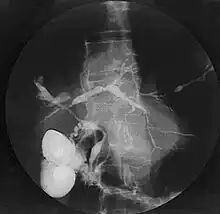

Cholangiogram of primary sclerosing cholangitis

Historically, a cholangiogram would be obtained via endoscopic retrograde cholangiopancreatography (ERCP), which typically reveals "beading" (alternating strictures and dilation) of the bile ducts inside and/or outside the liver. Currently, the preferred option for diagnostic cholangiography, given its noninvasive yet highly accurate nature, is magnetic resonance cholangiopancreatography (MRCP), a magnetic resonance imaging technique. MRCP has unique strengths, including high spatial resolution, and can even be used to visualize the biliary tract of small animal models of PSC.[21]